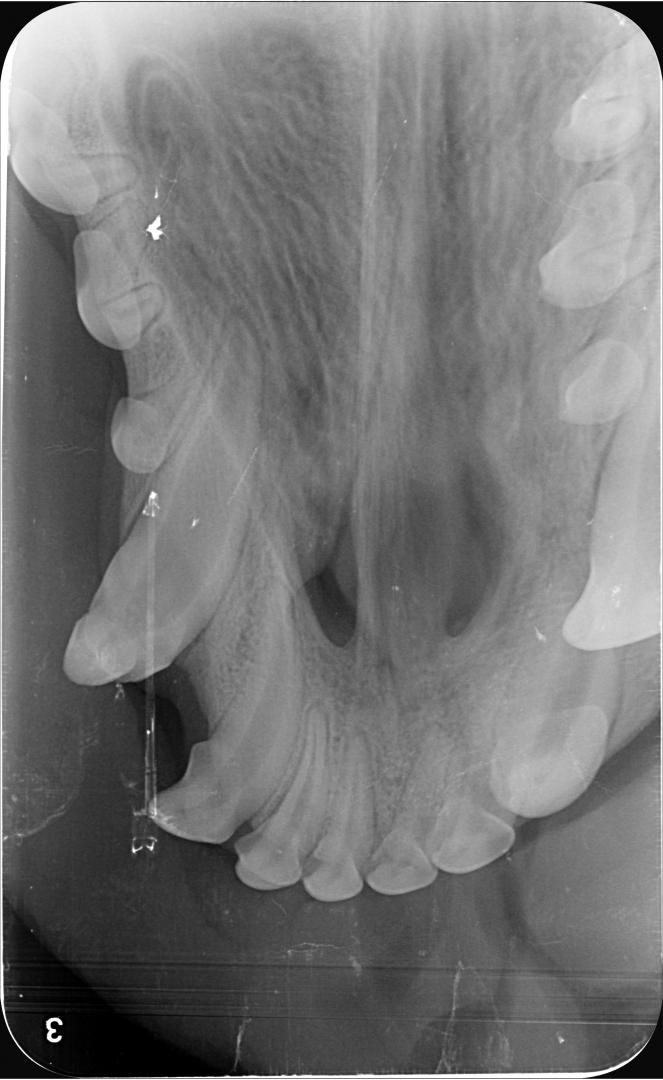

La radiographie est indispensable dans ce cas pour vérifier la meilleure conduite à tenir :

radio croc

Dans le cas d'Alphonse :

- l'apex est fermé (cercle vert) sur les 3 dents concernées ; aucun abcès n'est visible et donc la pulpe ne présente pas de signe de contamination (vérifié également par sondage, le canal n'est pas perméable)

- La couche de dentine semble déjà conséquente et suffisante pour donner une chance à la dent (trait bleu) ;

La décision est donc prise de tenter de la conserver, et de protéger la pulpe en déposant une couche de résine pour combler les surfaces abîmées du croc.